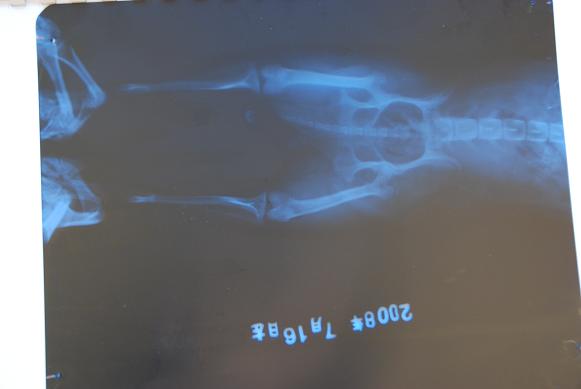

そして、お約束のラテのマル秘画像とは・・・。

↓↓↓

DSC_2937.JPG

レントゲン写真でした!!

素人が見ても全然わかりませんけどf(^^;)

あれ?でも足の先に何かありますねー?

DSC_2938.JPG

実はこれ私の手です。

押さえるのを手伝っていたら一緒に写っちゃいました・・・f(^^;)